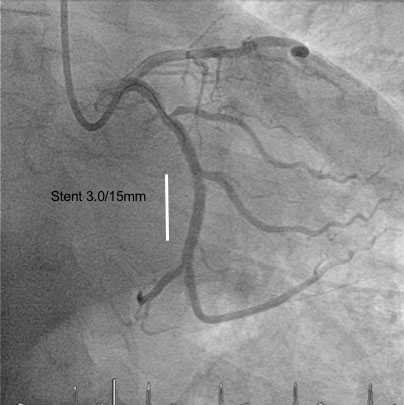

A total of 85/200 patients (42.5%) exhibited incidental findings requiring immediate further medical workup and/or treatment. Of note, most incidental findings here were newly diagnosed cardiovascular conditions, with coronary artery calcification being the most prevalent finding followed by arterial aneurysms and incidentally detected embolism (table 2, figs 1, 2a and 2b ). Pancreatic and liver tumours were less frequent, but significant. Examples of incidentally diagnosed tumours are shown in figures 3 and 4 .

Figure 2a Intra-arterial coronary angiogram showing a high-grade stenosis of the circumflex branch of the left coronary artery prior to drug eluting stent placement.

Figure 2b Intra-arterial coronary angiogram after drug eluting stent placement.